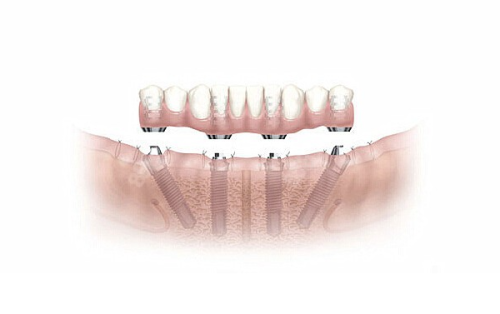

隐形种植牙其实是一种较为精良的牙齿修复方式。它和传统种植牙有相似之处,都是通过在牙槽骨内植入人工牙根,然后安装牙冠来修复牙齿功能。不过,隐形种植牙更注重美观和舒适度。它采用了特殊的材料和设计,在外观上几乎和真牙一样,旁人特别难察觉。而且在佩戴过程中,也不会有明显的异物感,就像自己原本的牙齿一样自然。对于那些对美观和舒适度有较高要求的患者来说,隐形种植牙是一个不错的选择。

舒适度好:隐形种植牙在设计上充分考虑了人体工程学原理。它的种植体和牙冠的连接非常紧密,不会出现松动或者晃动的情况。而且,它对口腔组织的刺激较小,患者在佩戴过程中几乎感觉不到异物感。相比传统的假牙,隐形种植牙在舒适度上有了较大的提升,能让患者更好地享受美食和正常的口腔功能。

稳定性强:隐形种植牙的人工牙根能够与牙槽骨紧密结合,形成稳定的支撑结构。这使得它在咀嚼食物时能够承受较大的力量,和真牙的功能非常接近。患者可以像使用真牙一样正常咀嚼各种食物,不用担心牙齿会出现问题。这种稳定性也确保了隐形种植牙的使用寿命相对较长,为患者提供了长期的牙齿修复解决方案。

适应人群:一般来说,单颗牙缺失、多颗牙缺失甚至全口牙缺失的患者都可以考虑隐形种植牙。尤其是那些对美观和舒适度要求较高,并且牙槽骨条件较好的患者,隐形种植牙能为他们提供理想的修复成效。比如一些年轻的患者,他们的生活和社交需求比较高,隐形种植牙可以满足他们对牙齿美观和功能的双重要求。